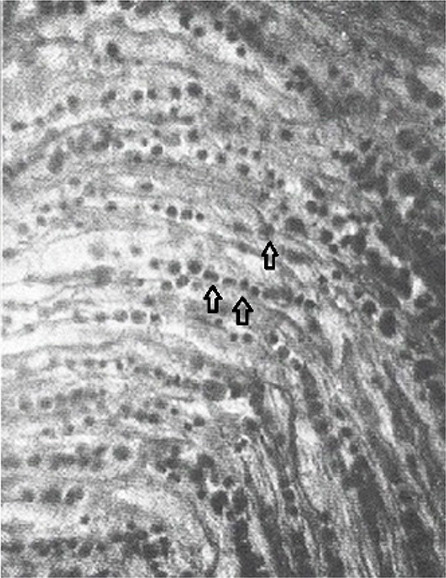

Marek's disease (MD) is a huge problem for researchers due to the significant losses in bird flocks, but more importantly, the virus's mutagenic potential. The purpose of this study was to describe non-classical gross lesions observed in broilers and laying hens that suggest the disease emergence and re-emergence. The survey was conducted on 10 broiler and 4 laying hen flocks. All of the dead birds were necropsied in order to obtain a comprehensive diagnosis of lesions, analysing both macroscopic and microscopic alterations. Marek's disease occurred in 80% of cases in broilers and 100% of cases in layer hens. The disease struck 26-day-old broilers and hens at 2 weeks of age, causing a total mortality of 6% and 15%, respectively. There were no clinical indications of the classical neurological form of the disease in either rearing type, and tumour lesions were mostly detected in the liver, spleen, and ovarian follicles in layers, and in the proventriculus in broilers. These findings demonstrated that MD is widespread and that its resurgence is primarily manifested in visceral rather than neurological manifestations. Despite MD immunization, biosecurity remains critical.